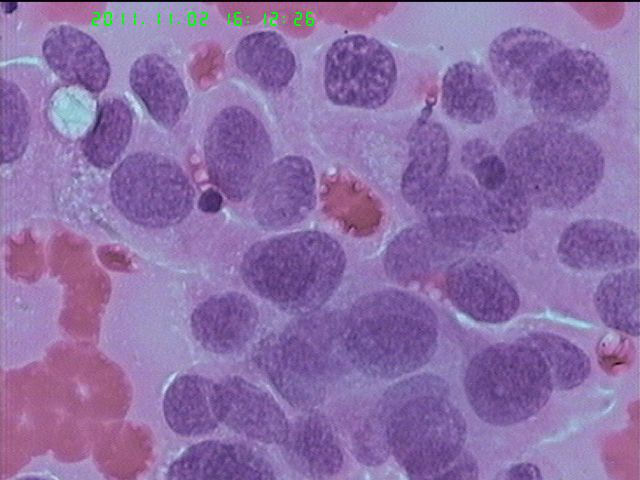

男65岁支气管刷片

鳞癌细胞

活检:鳞癌。

打癌没有问题,鳞腺的区分有时候非常困难。非小细胞癌。确实要分的话,打腺癌。好像癌有腺样趋势。

非小细胞肺癌,倾向为鳞癌可能性大。

查见恶性肿瘤细胞,首先考虑为大细胞性未分化癌。